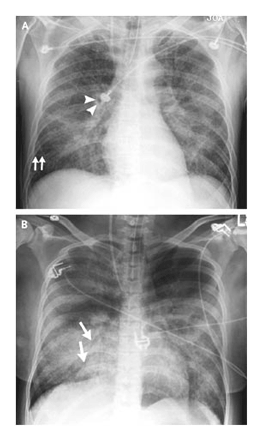

心源性和非心源性肺水腫發病機制不同,因此二者的后前位或便攜式前后位胸部X線片有某些可資鑒別的細微區別28-30(圖2)。1項研究對45例肺水腫患者進行了分析,其病因根據臨床和肺水腫液標本確定。在這項研究中,研究者采用基于胸部X線片特征(表1)的綜合評分,正確識別了87%的心源性肺水腫病人和60%的非心源性肺水腫病人。測量血管影的寬度有可能提高胸部X線片診斷的準確度,但其在心源性和非心源性肺水腫鑒別診斷中的實用價值還有待研究。

(圖2心源性和非心源性肺水腫患者的典型胸部X線片

A 幅是1例急性前壁心肌梗死和急性心源性肺水腫病人 (男性,51歲)的前后位胸部X線片。注意支氣管血管周間隙擴大(箭頭),間隔線(Kerley’s B線)明顯(箭),腺泡區的不透X線性增加,并融合成明顯的實變。外周相對不受累是心源性肺水腫的常見特征。B幅是1例肺炎并發膿毒癥性休克和急性呼吸窘迫綜合征病人(女性,22歲)的前后位X線胸片,血培養肺炎鏈球菌陽性。有伴支氣管含氣像(箭)的斑片狀浸潤和雙肺的彌漫性肺泡浸潤,這是非心源性肺水腫和急性肺損傷的特征,但并非其特異表現。雖然病變也累及左上葉,但受累相對較輕。無血管充血或肺血流重新分配證據。)